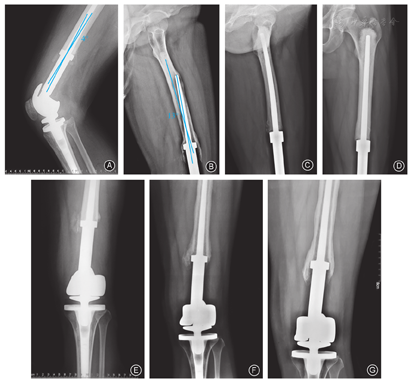

和西安交通大学机械工程学院机械制造系统工程实验室合作,取异体股骨段(西京医院骨科骨库提供)与翻修取出的假体在髓内行骨水泥固定,进行激光扫描,以点云数据形式导入Geomagic软件(Geomagic公司,美国)进行编辑处理,建立3D数学有限元模型,模型中在股骨顶部施加压力,压力大小相当于人的4倍体重(2 600 N)的情况下,然后改变压力施加的方向,指向4个方向,分别给3°和6°的偏置角度(图1),计算假体髓针横断面4个方向理论偏倚角度对松质骨的应变结果,分析得出假体髓针允许的偏倚自由度。

翻修假体在体外模拟体内的固定模型,基于有限元数学模型假体柄的计算机分析研究,在髓针4个方向改变髓针偏倚3°和6°两个角度,两个角度的改变对髓腔壁产生的形变分别为(0.590±0.001)mm和(1.163±0.002)mm,即增加髓针的偏倚角度,可使髓腔骨壁所受的形变明显增大,差异有统计学意义(t=409.5,P=0.000),说明偏倚角度越大骨壁形变越大,即假体松动的几率增加。

本组随访的病例共18例,均进行了松动前和松动后的影像学对照研究,观察发现13例假体柄和髓腔存在冠状位或矢状位匹配不满意,5例假体安装位置存在内、外旋。说明假体的自我修正过程会导致假体松动,而匹配满意者的假体使用寿命明显延长(图4)。

对影响股骨假体松动的多种相关因素进行分析,假体是否松动与患者性别、年龄、职业及假体的类型无明显相关(P>0.05,表2)。而瘤段的截骨长度与假体松动明显相关(χ2=8.968,P=0.0027),截骨长度>12 cm者较截骨长度<12 cm者假体更容易松动。假体松动与假体力线偏移角度明显相关(χ2=18.45,P=0.000),研究表明在矢状位,假体力线偏移角度>3°的患者的假体较假体力线偏移角度<3°的患者的假体更容易松动。

本组共对16例股骨下端肿瘤型假体患者术后1年进行步态分析,当改变肿瘤膝关节假体在冠状面内的偏置角度后,健侧髋、膝关节力极差比均<5%,患侧下肢髋关节的极差比为17.62%±9.7%,膝关节98.18%±23.2%,极差比平均值均>5%;当改变肿瘤膝关节假体在矢状面的偏置角度后,双侧髋、膝关节力极差比<5%。这一结果表明,改变假体冠状面的偏置角度时,置换侧关节力增幅明显(图5)。